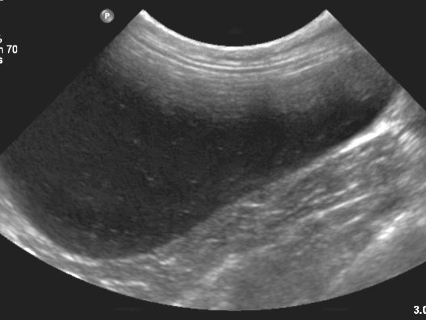

4 - Est ce que l’image obtenue vous semble correcte ?

A - Oui

B - Non

C - Je ne sais pas

5- Si non, expliquez quel réglage serait intéressant de modifier pour obtenir une image échographique correcte

A - J'ai coché oui à la réponse précédente

B - Diminuer la profondeur

C - Augmenter la profondeur

D - Augmenter le gain étagé en profondeur

E - Diminuer le gain étagé en profondeur

6- De quel organe s’agit-il ? Précisez G ou D et le plan de coupe réalisé

A - Le Rein Gauche en coupe transversale

B - Le Rein Droit en coupe transversale

C - Le Rein Gauche en coupe longitudinale

D - Le Rein Droit en coupe longitudinale

E - La Surrénale droite en coupe transversale

Question 4 : Réponse B

Question 5 : Réponse B

Question 6 : Réponse C

Question 7 : Réponse A